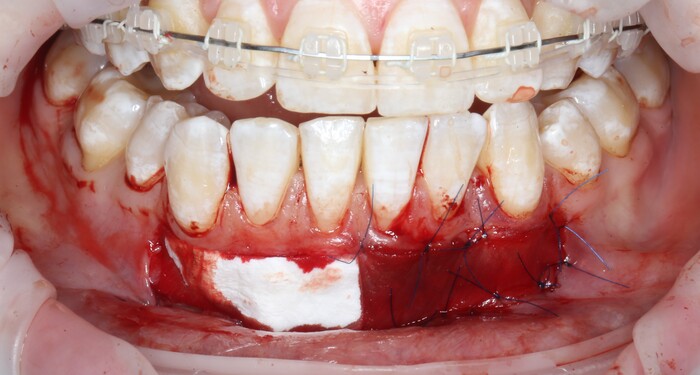

2 – проведение пластики десны.

Был взят трансплантат в области бугра верхней челюсти (это то место, где раньше был зуб мудрости).